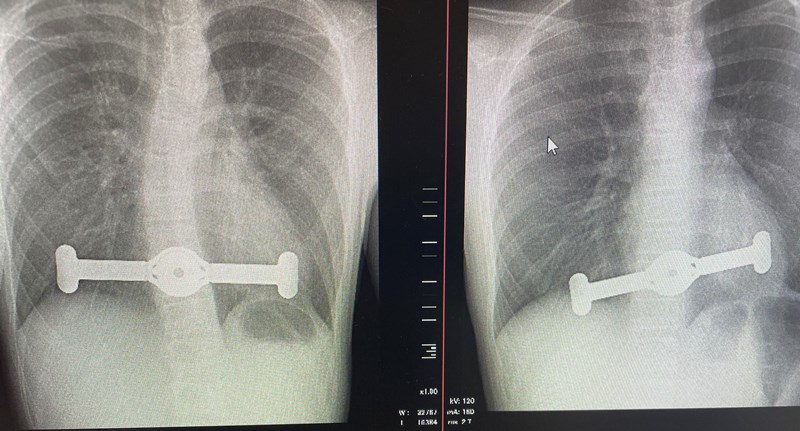

Krūtinės ląstos įdubimo operacija. Rentgeno nuotrauka

Į vidų išsivertęs krūtinkaulis, kitaip tariant, įdubusi krūtinė, – ne tik estetinė problema, su kuria dažniausiai susiduriama nuo gimimo. Didelė krūtinės ląstos įduba gali mechaniškai spausti širdį ir šitaip trikdyti jos veiklą. Kai kuriais atvejais įdubusi krūtinė atsiranda ir po atviros širdies operacijos. Tokio tipo krūtinės ląstos deformaciją pasaulyje turi 2–3 procentai gyventojų, Lietuvoje per metus atliekama maždaug 30 chirurginių operacijų įdubusiam krūtinkauliui koreguoti.

Nors naujausi medicininiai implantai (plokštelės) tradicinių strypų, kurie buvo naudojami iki šiol, visiškai pakeisti negali, daugeliui pacientų, ypač vaikams, korekcija plokštelėmis yra saugesnė, paprastesnė ir gali būti sėkmingai taikoma. Svarbiausia, konsultacijos kreiptis į specialistą, kuris, apžiūrėjęs pacientą, atlikęs kompiuterinę tomografiją, įvertins gautus parametrus ir pasiūlys tinkamiausią problemos sprendimo būdą.

Santaros klinikų Vaikų ortopedijos ir traumatologijos skyriaus vedėjas ortopedas traumatologas Giedrius Bernotavičius pirmasis Baltijos šalyse dviem keturiolikmečiams atliko įdubos krūtinės korekciją naujuoju būdu. Gydytojas džiaugiasi, kad procedūra naujaisiais implantais – plokštelėmis – yra ne tik saugesnė, bet ir mažai invazyvi, todėl gerokai paprastesnė. Procedūra trunka iki valandos, gijimas nepasižymi dideliu skausmu ar ilga reabilitacija: iš ligoninės pacientai išleidžiami po paros ar dviejų ir greitai sugrįžta į kasdienį gyvenimą.

„Po dvejų ar trejų metų krūtinės ląsta pamažu susitvarko, implantai išimami, ir, kaip tikina gamintojai, dar nėra buvę atvejų, kad krūtinės ląsta vėl deformuotųsi. Standartinis atvejis, kai procedūrai atlikti naudojamas strypas, kur kas labiau traumuojantis, todėl tikimės, kad plokšteles bus galima taikyti daugeliui vaikų ir suaugusiųjų. Reikia žinoti, kad vyresniame amžiuje krūtinės ląstą ne taip lengva koreguoti, negana to, brandaus amžiaus pacientą gali varginti kaulų retėjimas, todėl kiekvienu atveju, ryžtantis chirurginei intervencijai, būtina įvertinti riziką“, – tikina ortopedas traumatologas G. Bernotavičius.